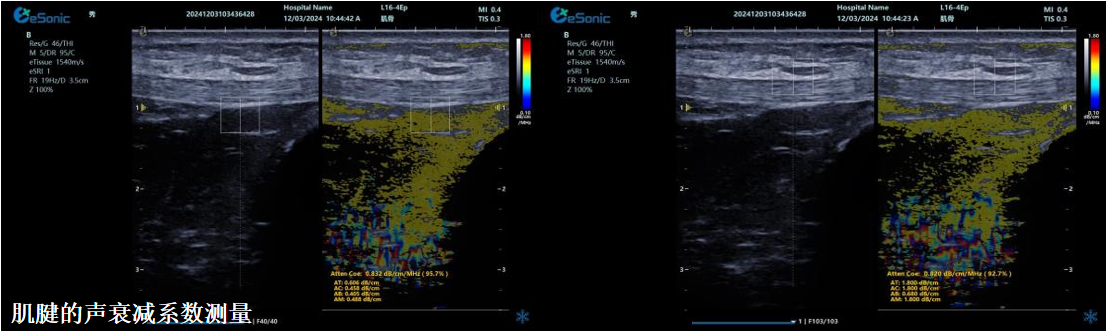

ATI高级声衰减成像

?独有的幅度损失的衰减方法ALA,准确性高,稳定性好,实时性好?业界唯一支持凸阵与线阵两种探头?支持多个取样框?提供两种显示单位

肌骨领域的应用

?肌腱炎症或损伤的评估?肌肉拉伤的定位?关节磨损或炎症的诊断?骨质疏松的早期发现和监测